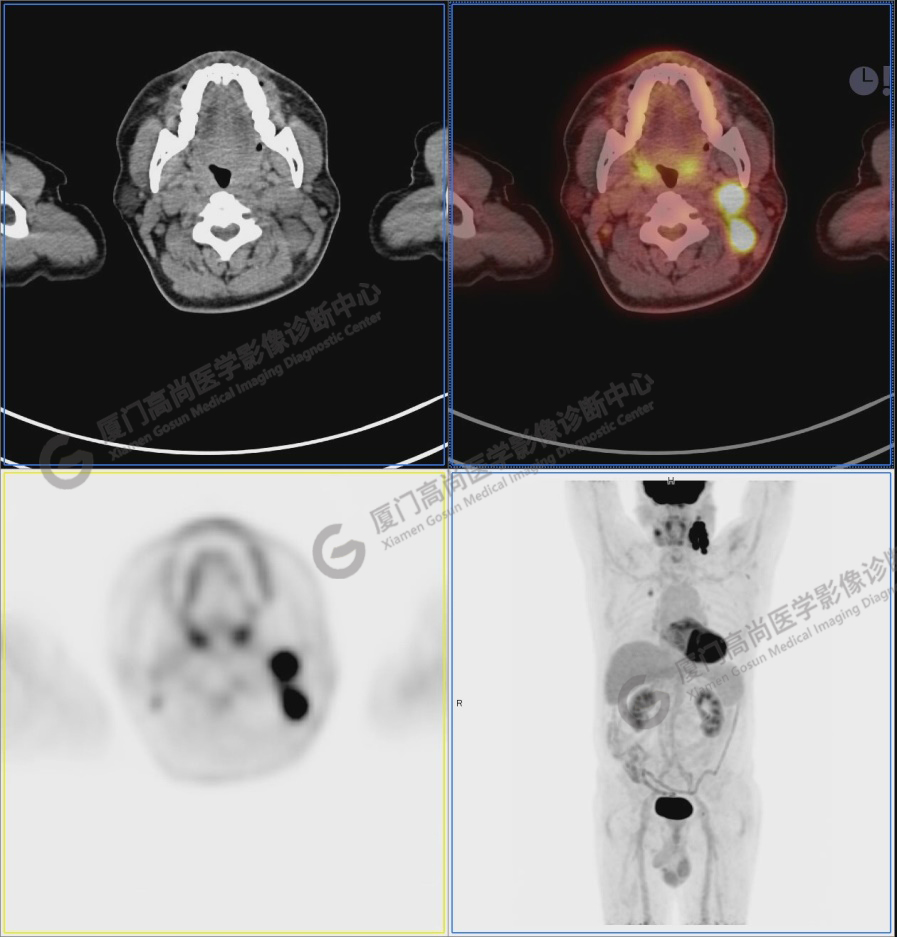

PET/CT影像圖

圖1:PET/CT全身圖像

圖2:雙側(cè)頸部多發(fā)增大淋巴結(jié),代謝不同程度增高,考慮為轉(zhuǎn)移。

圖6-9:鼻咽左側(cè)壁增厚,代謝異常增高,考慮為鼻咽癌